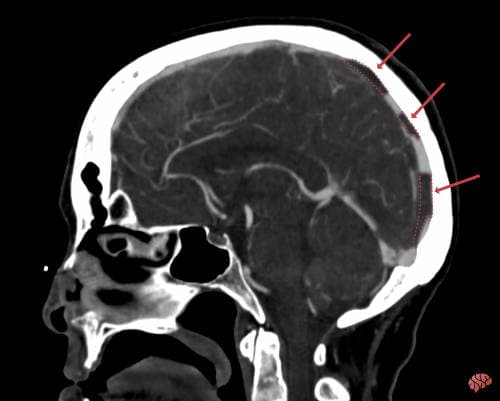

Vários exames de imagem podem detectar a trombose.

Em alguns casos, a tomografia de crânio simples já pode levantar a suspeita ao mostrar o trombo como uma lesão branca (que chamamos de hiperdensidade) na região onde deveria estar circulando sangue. Além disso, existem alguns padrões de sangramento ou isquemia que indicam a possibilidade de trombose.

Outra vezes, só é feito o diagnóstico com exames específicos, como a angiotomografia venosa e, principalmente, a angioressonância venosa por ressonância magnética.

Esses exames podem identificar o trombo e a falta de circulação de sangue na sua localização, como na imagem acima. Em casos de dúvidas, a angiografia cerebral por cateter pode ajudar, mas geralmente é realizada apenas em casos específicos.